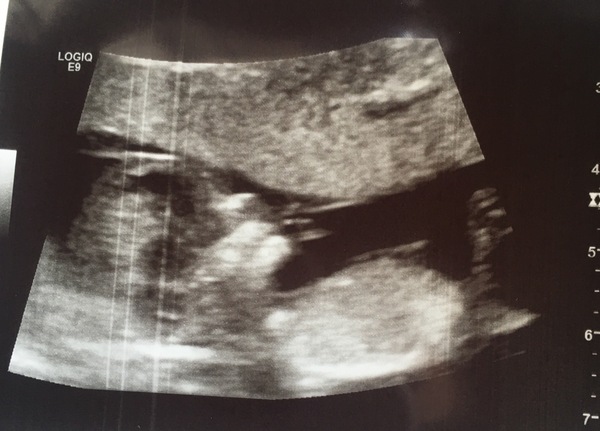

Some good news here... I just had my dating scan - all looks well, nuchal of 1.2 and giving me a due date of June 7th.

Little bean was super active, moving all over the place, waving arms and legs. She showed me the brain and said all the other organs looked good too. So relieved. Now just the wait for the combined results 😬

So happy for you @MadeInCornwallx3, that's a fab scan pic :) x

@MadeInCornwallx3 what a beautiful scan picture and great to hear all is looking well 😊

That’s a great scan pic @madeincornwallx3